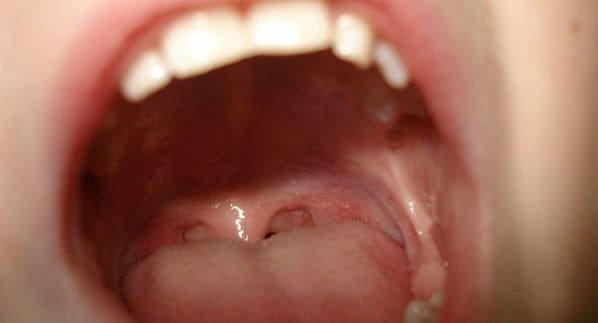

Las llagas se identifican por ser pequeñas heridas redondeadas con un tono amarillento o blanquecino en el centro y rojizas en los bordes que causan dolor y escozor. Además de las molestias obvias del lugar en el que se encuentren, pueden producir malestar general o incluso fiebre. En el caso de aparecer en la garganta, pueden llevar a que aparezcan ganglios en el cuello.

Las llagas en la garganta provocan otros efectos al margen de los evidentes ya que causan muchas molestias a la hora de comer, beber o hablar. Estas molestias se manifiestan en forma de dolor y ardor que pueden llegar a ser realmente intensos.